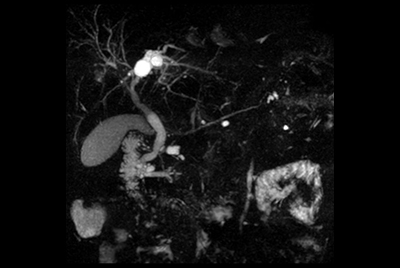

Liver with MRCP